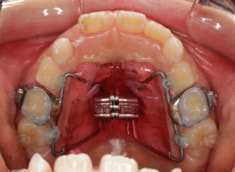

治療開始時